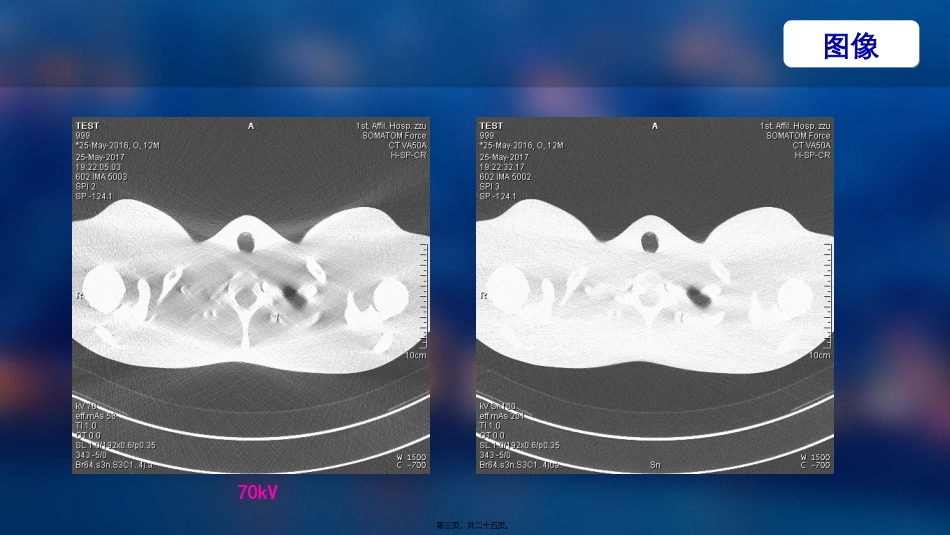

能谱纯化在胸部CT的应用ChestCTusingspectralfiltration刘杰2022.07.12第一页,共二十五页。图像120kV第二页,共二十五页。图像70kV第三页,共二十五页。研究目的Todeterminetheradiationdose,imagequality,andclinicalutilityofnon-enhancedchestCTwithspectralfiltration.即将该新技术与普通胸部平扫在如下三方面做比照辐射剂量Radiationdose图像质量Imagequality临床应用Clinicalutility第四页,共二十五页。ALARAprincipleaslowasreasonablyachievableHowmuchdosereductionisreasonable?VSadetailedassessmentofinterstitiallungdiseaseanexaminationperformedforlungnoduledetectionrequireasignificantlyhigherdose研究背景第五页,共二十五页。In2022,athird-generationdual-sourceCTsystemwasintroduced.第三代双源CT问世Thissystemfeaturesatinfilter,whichcanbepositionedinfrontofbothX-raytubes,andwhichabsorbsprimarilylow-energyphotonsthatcontributelittletoimagequalitybutincreasethedoseofradiationthatapatientreceives.用该研究来证实研究背景第六页,共二十五页。Keypoints•Spectralfiltrationenablesnon-contrastchestCTwithveryhighdoseefficiency.•ThisapproachreducesCTDIvol,DLP,andSSDE(effectivechestdiameter28cm).•Lungnodules,pneumonia,andpleuralpathologiescanbeassessedwithuncompromisedconfidence.关键点第七页,共二十五页。25non-contrastchestCTexaminationsacquiredwithspectralfiltration(tin-filteredSn100kVpspectrum)25non-contrastchestCTexaminationsacquiredwithoutspectralfiltration(120kV).研究方法实验组对照组图像质量评估内容3.Contrast-to-noise-ratio(CNR)4.figure-of-merit(FOM)5.Diagnosticconfidence1.Radiationmetrics2.Imagenoise第八页,共二十五页。CTacquisitionprotocol研究方法第九页,共二十五页。StatisticalanalysisMedCalcSoftware,Ostend,BelgiumKolmogorov–SmirnovtestMann–Whitneytestschi-squaretestPvalues<0.05Kappastatistics所用软件:所用方法:柯尔莫可洛夫-斯米洛夫检验曼-惠特尼检验第十页,共二十五页。Patientselection第十一页,共二十五页。Radiationmetrics第十二页,共二十五页。Diagnosticconfidenceandmotionartefacts——主观评价内容pneumoniadiffuseparenchymallungdisease(e.g.,emphysema,interstitiallungdiseases)pulmonarynodulespleuralpathologies(e.g.,pneumothorax,pleuraleffusion,andpleuralthickening)osseouspathologiesmediastinalabnormalities(e.g.,mediastinallymphadenopathy)第十三页,共二十五页。Subjectiveassessmentofdiagnosticcondifence第十四页,共二十五页。Motionartefacts第十五页,共二十五页。minorcardiacmotionartefactsmajormotionartefactsinthebasallungs第十六页,共二十五页。Picturea,bwithouttin-filterImagequalityiscomparable---despiteasubstantialdosereductionwithtinfiltrationEXAMPLE第十七页,共二十五页。Differentpathologiesareshownonnon-contrastchestCTimagesacquiredwithspectralfiltrationonthenovelthird-generationdual-sourceCTsystematypicalpneumonia(a,b)lobarpneumonia(c,d)pulmonarynodules(f)pleuralcalcifications(e)第十八页,共二十五页。结论Despiteincreasedimagenoise,spectralfiltrationCTprovidedsufficientdiagnosticconfidencefortheassessmentofpneumonia,pulmonarynodules,andpleuralpathologies,whilesubstantiallyreducingradiationdose.第十九页,共二十五页。Theprotocolappearssuitableforlungcancerscreeningandforsurveillanceofincidentallydetectedlungnodules讨论&猜测Althoughourstudydidnotevaluatethistechniqueinchildren,spectralfiltrationCTmayalsobeofgreatinterestforpediatricchestCT引申一:该研究也适用于肺癌患者的扫描与发现肺结节引申二:更适合儿童胸部CT〔与儿童Flash序列做比照〕第二十页,共二十五页。原理第二十一页,共二十五页。1、这是一篇很常见的低剂量胸部文章2、时效性很强3、加入了对疾病应用范围的研究4、三种及三种以上的统计学方法不平凡第二十二页,共二十五页。1、Sn100与常规胸片在发现肺部病变的能力2、Sn100在儿童中常规应用3、Sn100与Sn150在不同BMI下的应用探讨4、Sn100在鼻窦低剂量的应用启发&疑惑第二十三页,共二十五页。THANKS!刘杰2022.07.12第二十四页,共二十五页。内容总结能谱纯化在胸部CT的应用。2022.07.12。interstitiallungdisease。anexaminationperformed。(tin-filteredSn100kVpspectrum)。CTacquisitionprotocol。引申二:更适合儿童胸部CT〔与儿童Flash序列做比照〕第二十五页,共二十五页。

您可能关注的文档